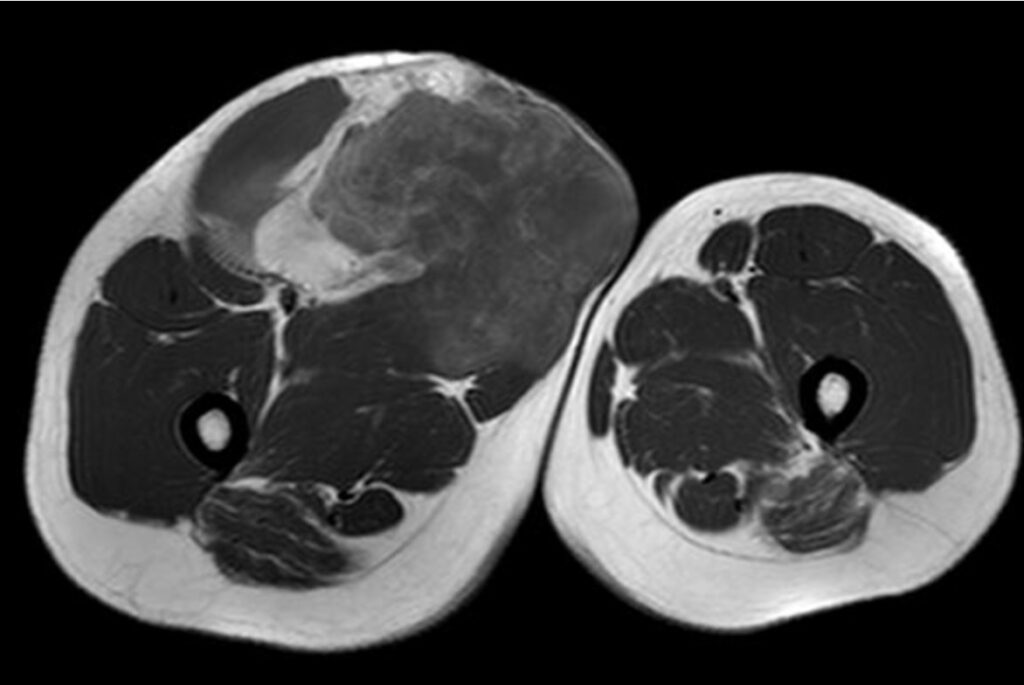

Lipossarcoma: este tipo de câncer é originado do tecido gorduroso do corpo, frequente em pacientes adultos e idosos. A localização mais frequente é a coxa, seguido dos demais membros e retroperitônio. Tem o aparecimento insidioso podendo atingir grandes volumes, merece atenção especial devido ao alto potencial de metástases à distância.